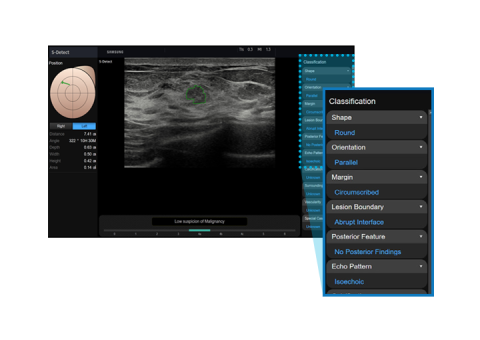

The feature, which analyzes selected lesions in the breast ultrasound study and shows the analysis data, applies BI-RADS ATLAS* (Breast Imaging-Reporting and Data System, Atlas) to provide standardized reporting; and helps diagnosis with the streamlined workflow.

* It is a registered trademark of ACR and all rights reserved by ACR.